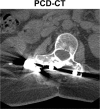

Photon-counting detector (PCD) CT is an emerging technology that has shown tremendous progress in the last decade. Various types of PCD CT systems have been developed to investigate the benefits of this technology, which include reduced electronic noise, increased contrast-to-noise ratio with iodinated contrast material and radiation dose efficiency, reduced beam-hardening and metal artifacts, extremely high spatial resolution (33 line pairs per centimeter), simultaneous multienergy data acquisition, and the ability to image with and differentiate among multiple CT contrast agents. PCD technology is described and compared with conventional CT detector technology. With the use of a whole-body research PCD CT system as an example, PCD technology and its use for in vivo high-spatial-resolution multienergy CT imaging is discussed. The potential clinical applications, diagnostic benefits, and challenges associated with this technology are then discussed, and examples with phantom, animal, and patient studies are provided. ©RSNA, 2019.